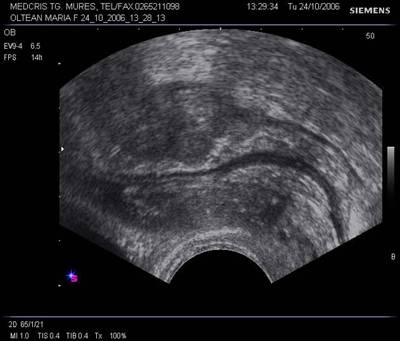

Fig. Nr.341. Sectiune longitudinala prin pelvisul feminin